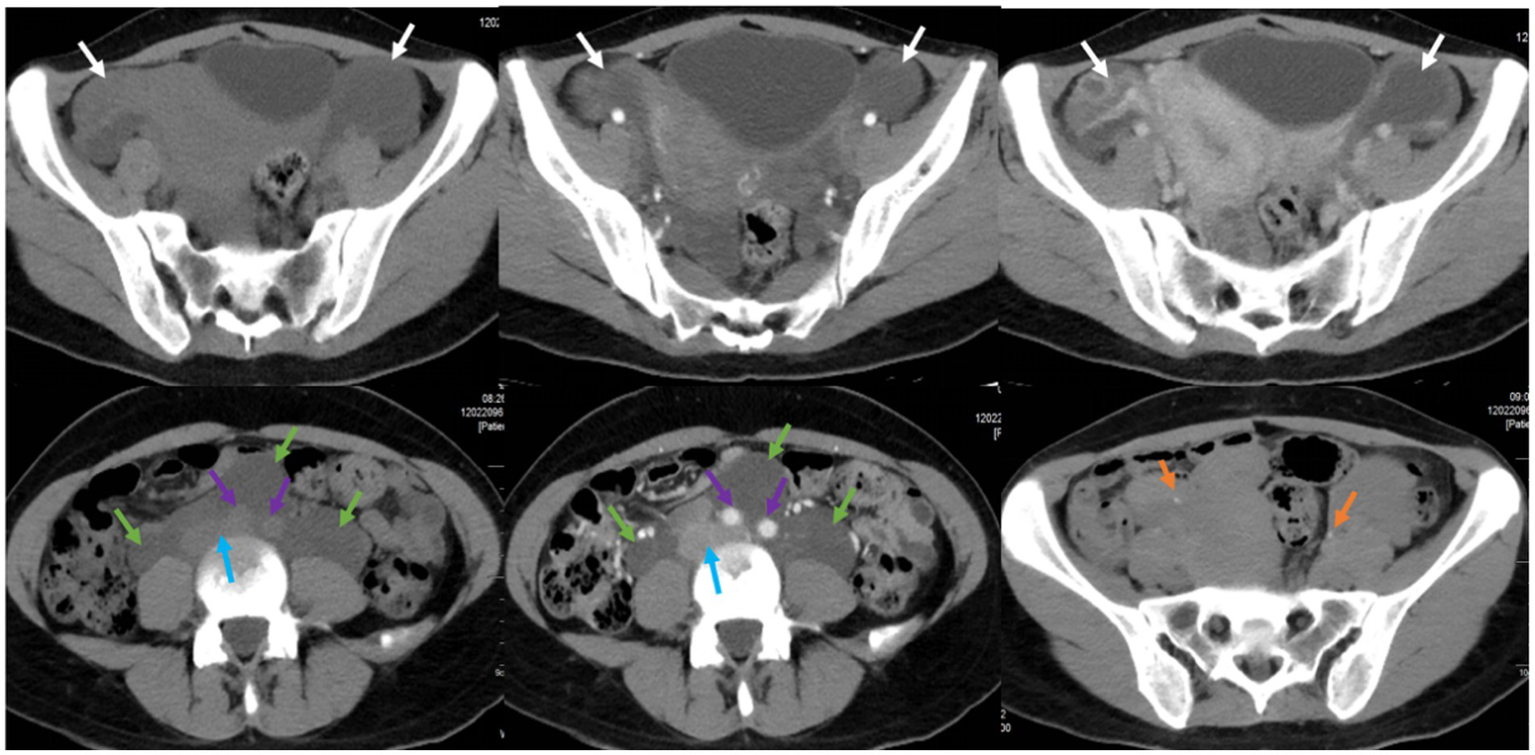

Furthermore, the patient underwent additional imaging evaluations, including pelvic enhanced CT (Figure 2), enhanced pelvic Magnetic Resonance Imaging (MRI; Figure 3), computed tomography urography (CTU), and three-dimensional reconstruction (Figure 4). The results revealed heterogeneous enhancement of bilateral ovaries and a widespread cystic-solid mass in the pelvic and retroperitoneum. The upper edge of the cystic part reached the level of the renal artery, wrapping around the abdominal aorta, inferior vena cava, iliac artery, and vein, while embedding the middle and lower part of the ureter. Importantly, the shape and density of both kidneys were normal.

Figure 2

Pelvic CT plain scan and enhancement in a pregnant woman seen at Shanghai First Maternity and Infant Hospital Affiliated with Tongji University. The white arrow points to bilateral ovaries, the green arrow points to the cystic-solid mass, the blue arrow points to the abdominal aorta, the purple arrow points to the inferior vena cava and iliac vessels, and the yellow arrow points to the ureters.